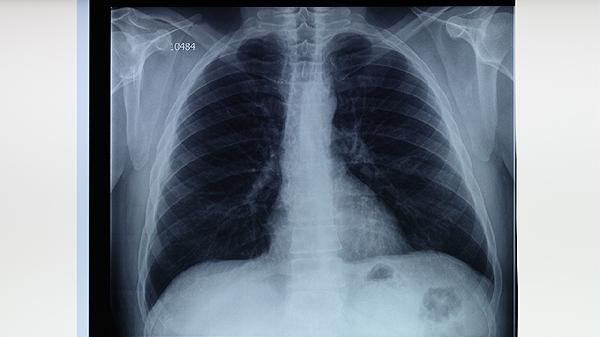

肺結(jié)核早期可通過(guò)生活干預(yù)、藥物治療、手術(shù)治療等方式治療。肺結(jié)核通常由結(jié)核分枝桿菌感染引起,早期可能表現(xiàn)為咳嗽、低熱、盜汗等癥狀。